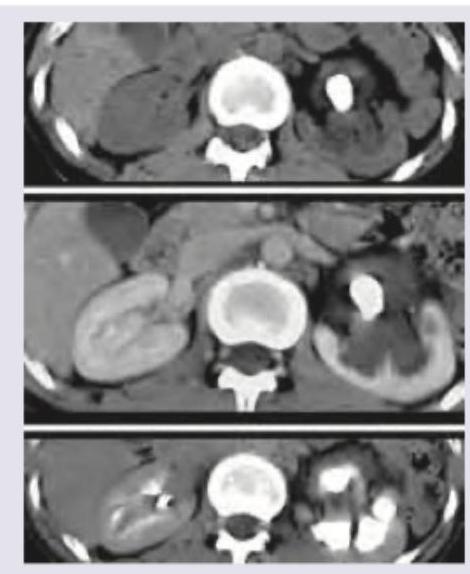

A 40-year-old alcoholic presents with severe epigastric pain and hemodynamic collapse. CT abdomen was performed after fluid resuscitation which shows: (Recent NEET Pattern 2016-17)

Explanation: ***Severe acute pancreatitis*** - The CT scan shows significant **peripancreatic fat stranding** and **fluid collections** (indicated by arrowheads), which are hallmark features of acute pancreatitis - The presence of **hemodynamic collapse** with extensive peripancreatic inflammatory changes indicates **severe acute pancreatitis** (previously called necrotizing pancreatitis) - Clinical context: **alcoholic patient** with severe epigastric pain and shock—classic presentation requiring ICU care - The **revised Atlanta classification** defines severe acute pancreatitis by the presence of organ failure (hemodynamic collapse = cardiovascular failure) *Acute pancreatitis* - While the CT undeniably shows acute pancreatitis, this option is **too non-specific** given the clinical severity - The presence of **hemodynamic collapse** (organ failure) by definition classifies this as **severe** acute pancreatitis, not simple acute pancreatitis - Missing the severity classification could lead to underestimation of disease gravity and inadequate management *Perforation peritonitis* - Would typically show **free intraperitoneal air** (pneumoperitoneum) on CT, which is absent here - The CT findings are specifically pancreatic: **peripancreatic inflammation and fluid collections**, not diffuse peritoneal contamination - While severe epigastric pain and collapse can occur with perforation, the imaging is diagnostic for pancreatic pathology *Pseudo-pancreatic cyst* - Pseudocyst is a **late complication** of acute pancreatitis, typically forming **4-6 weeks** after the initial attack - Represents a **mature, well-defined fluid collection** with a fibrous wall, not acute inflammatory changes - The patient's **acute presentation** with immediate pain and hemodynamic collapse, along with diffuse peripancreatic inflammatory changes (not a discrete encapsulated collection), excludes this diagnosis